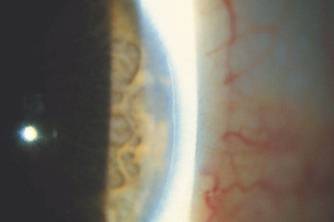

2. True statements about the following corneal condition include:

a. it occurs at the junction between the Descemet's membrane and the endothelium

b. it has an autosomal dominant inheritance

c. glaucoma occurs in 90% of cases

d. it is a feature in Chandler's syndrome

e. it occurs in Peter's anomaly